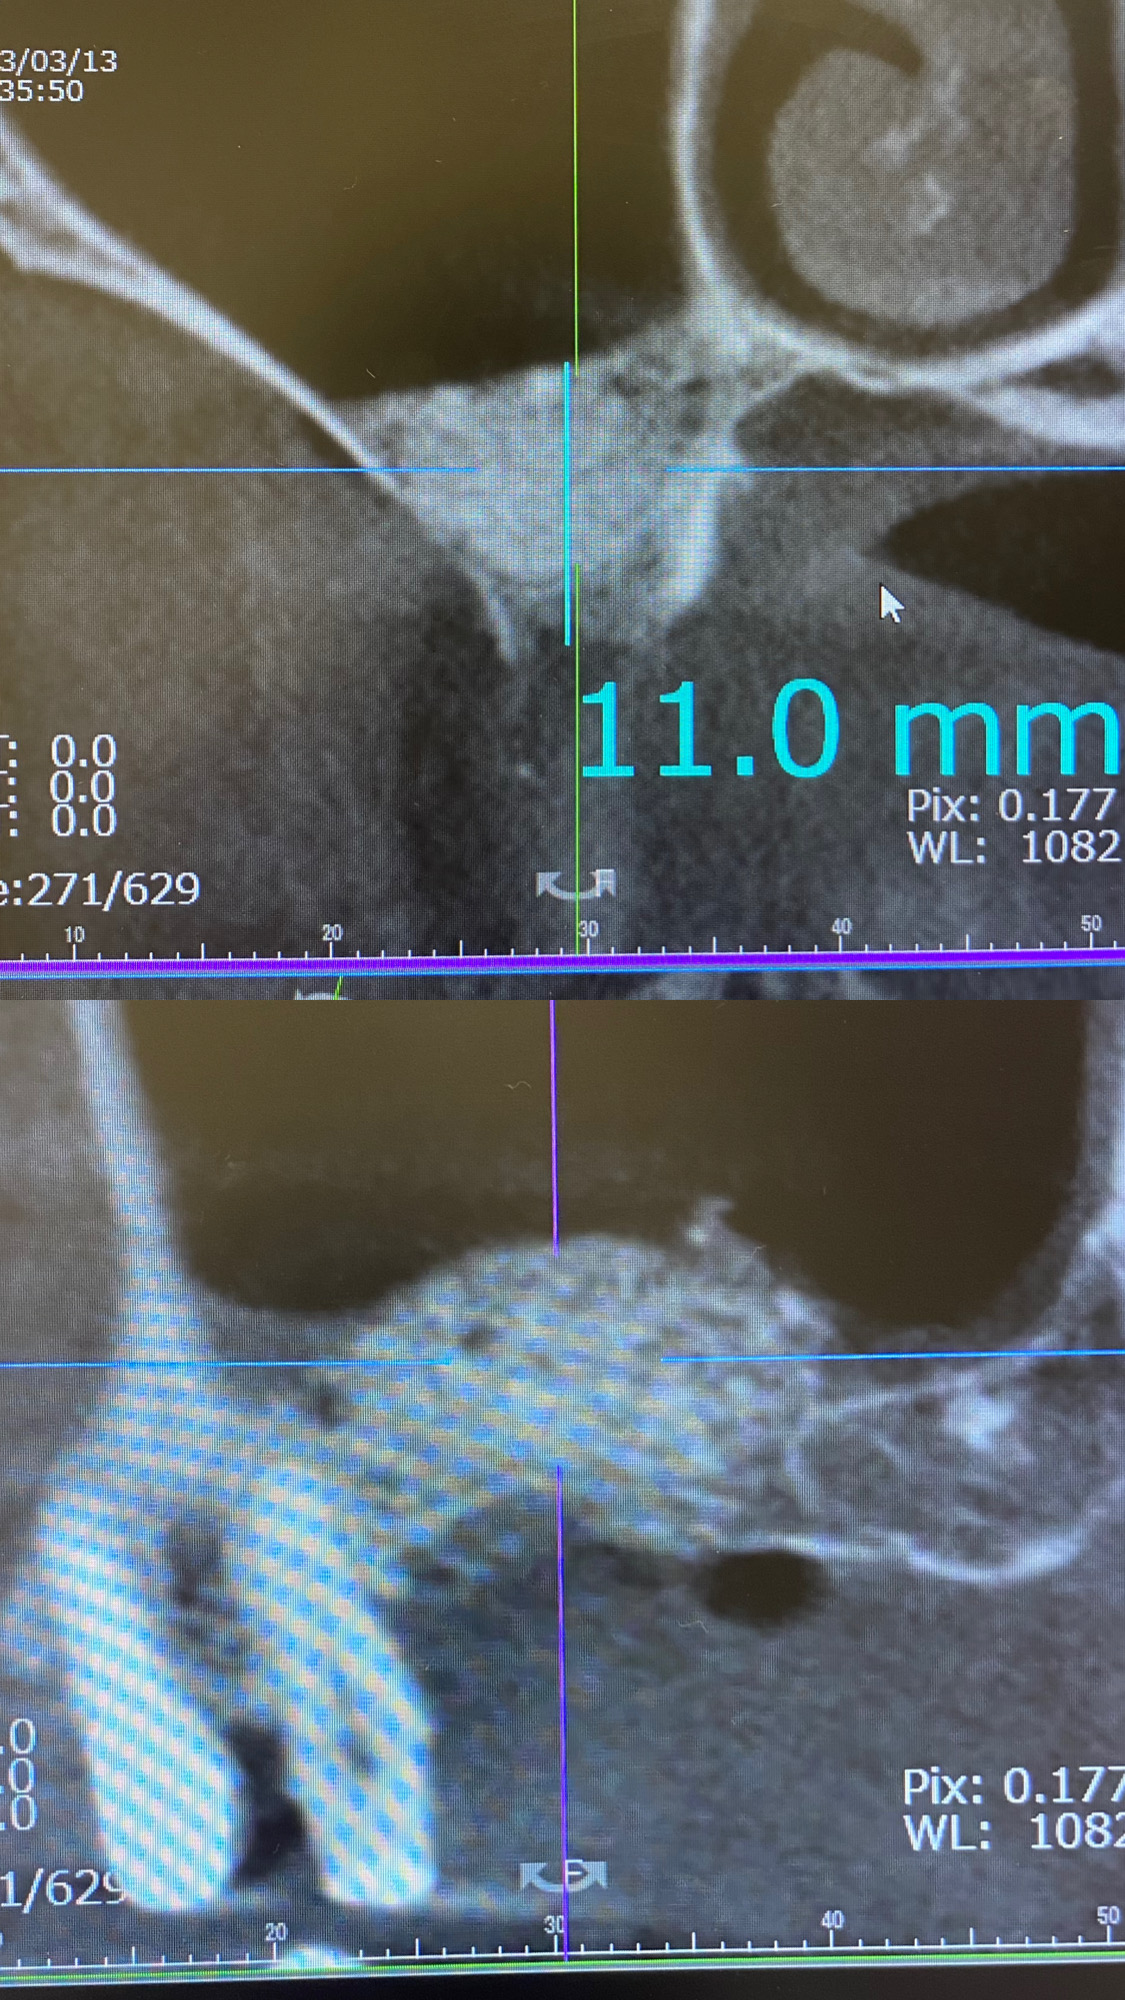

写真は当院でサイナスリフトを行った後のCTです。

サイナスリフトとは、インプラント治療の際上顎奥歯にに広範囲にわたって骨を増やす必要がある時に行う治療です。

この時にも患者様の年齢を考えて生涯インプラントを使っていただくために、骨を増やす量を決める必要があります。

そのためにサイナスリフトやGBRなどの治療が必要となります。